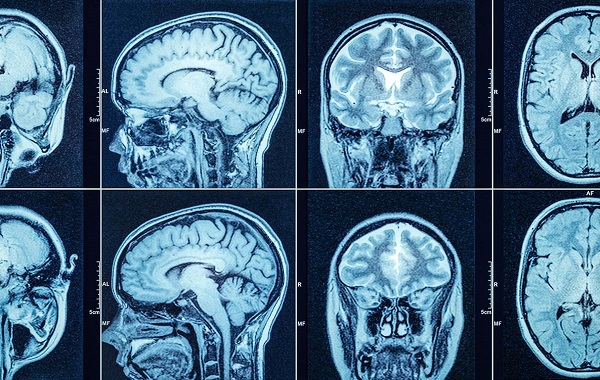

- Chụp CT hoặc MRI.